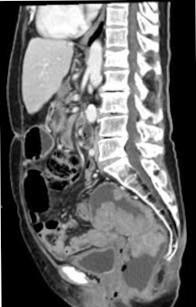

The authors present the case of a 79-year-old woman who presented with chronic secretory diarrhoea and severe electrolyte imbalance. A large rectal tubulovillous adenoma was discovered, leading to surgical resection of the tumour with complete resolution of the diarrhoea and electrolyte imbalance. The diagnosis of McKittrick-Wheelock syndrome was made. We hope this case report will contribute to a greater awareness among health professionals about this clinical condition. A multidisciplinary approach is essential for the best outcome.

作者报告了一例79岁女性患者,该患者表现为慢性分泌性腹泻和严重电解质失衡。发现一个巨大的直肠绒毛管状腺瘤,手术切除肿瘤后腹泻和电解质失衡完全缓解。诊断为麦基特里克 - 惠洛克综合征。我们希望本病例报告能提高卫生专业人员对这种临床病症的认识。多学科方法对于获得最佳治疗效果至关重要。